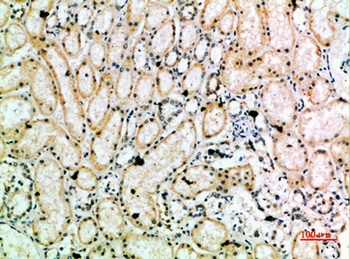

应用稀释比例:IHC-p 1:50-200, ELISA 1:10000-20000

ELISA, IHC-P